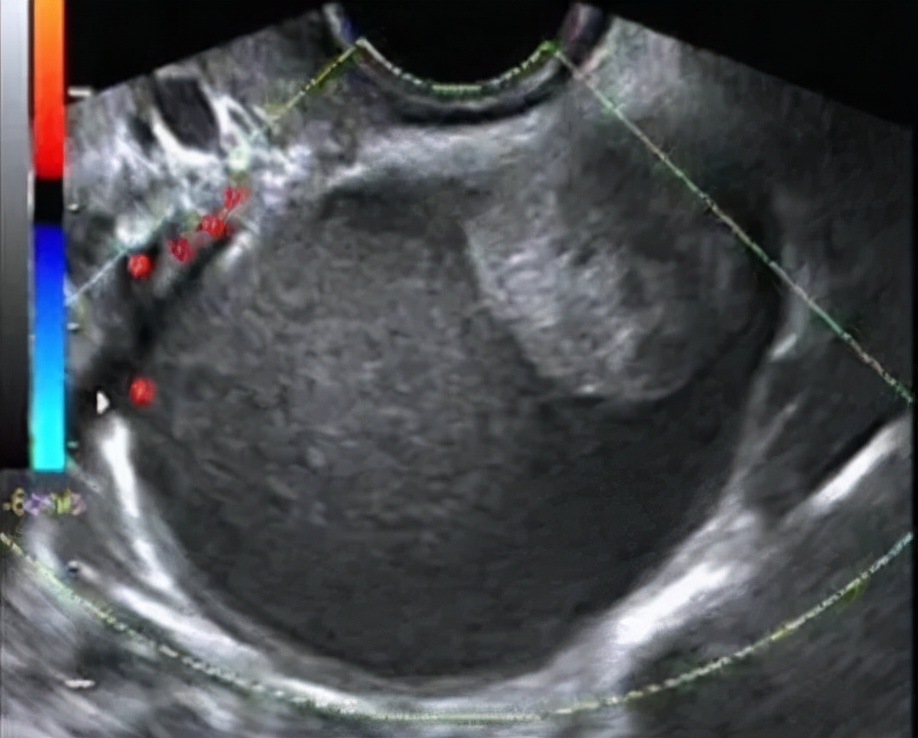

黄体血肿特点: 囊内回声不均匀,有多种表现,比如杂乱回声、网状结构、实性稍高回声,甚至有密集的光点样强回声。一般会自然消退,同样建议1-3个月后月经干净3天左右复查。